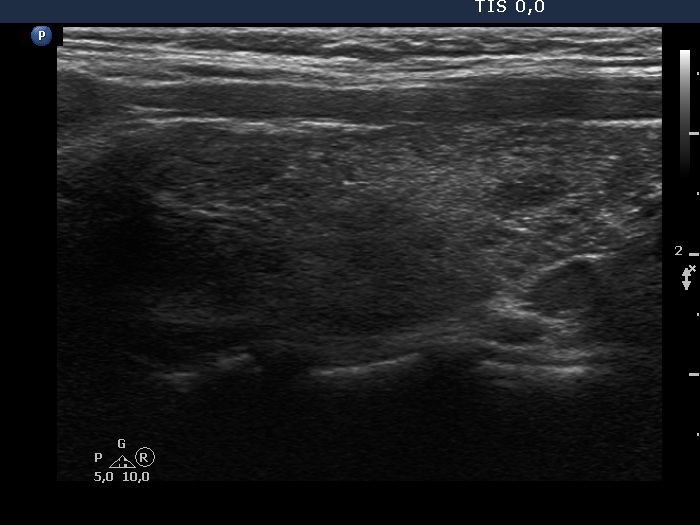

Right lobe, longitudinal scan

Upper 3/4 of the right lobe, longitudinal scan. The pattern corresponds to Hashimoto's thyroiditis.